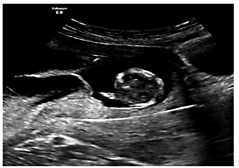

We believe that optimally there should be a rigorous evaluation of fetal status as part of the decision process prior to reduction, which includes more than just nuchal translucency ultrasound and position of the fetuses. Typically, we perform a 2-day procedure on most patients at about 12 weeks of gestation: CVS on the first day with FISH analyses overnight for chromosomes 13, 18, 21, X, and Y [38] (fig. 5). We get the results back the next afternoon, and can then do the reduction that day. By definition, FISH for 5 chromosomes cannot detect everything, but our experience and modeling suggest only about a 1/400 residual risk of a problem on karyotype [38] - which we believe to be a lower risk than sending the patient home to return nearly 2 weeks later and risk loss from the higher-order multiple with potential confusion as to which embryo/fetus was which on the ultrasound [48,49].

Transcervical CVS on triplet. Catheter with stylet in place seen as a white line traversing lower placenta.